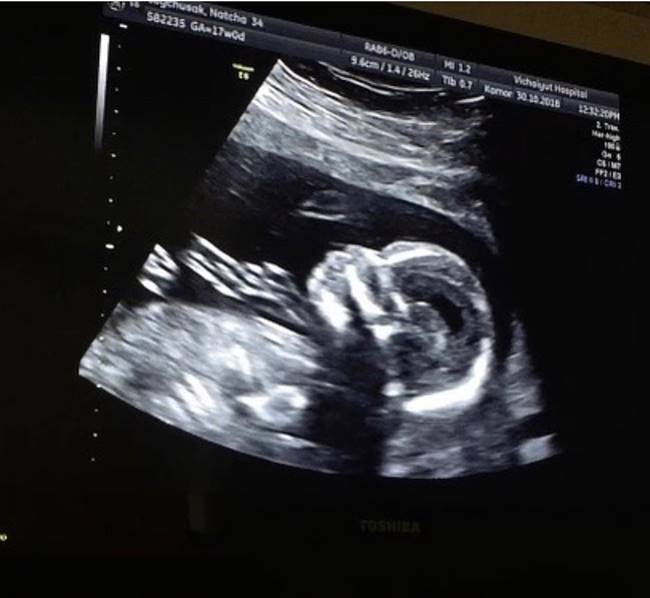

เจมส์ เรืองศักดิ์ เผยภาพอัลตราซาวด์ 4D น้องเมดา พร้อมเผยที่มาที่ตั้งชื่อให้ลูกสาวว่า อันโดรเมดา มาจากนางในวรรณคดี วิวาห์พระสมุทร ของล้นเกล้ารัชกาลที่ 6

พฤศจิกายน 2561) คุณพ่อเจมส์ ได้เผยภาพอัลตราซาวด์ลูกสาวแบบ 4D

เผยให้เห็นภาพชัด ๆ ของเบบี๋น้อย